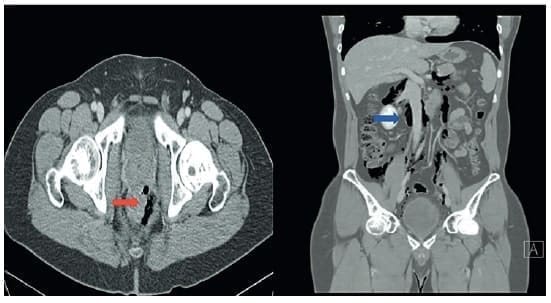

Es importante tener en cuenta que la presencia de colecciones de gas asimétricas y focales en el recto debe alertar sobre la posibilidad de un trauma rectal, aún en los traumas penetrantes 12 (Figura 1).

Figura 1. Tomografía computarizada (TC) de abdomen y pelvis contrastada que muestra múltiples burbujas de aire atípico en la grasa para rectal en la cara anterior y lateral izquierda. En la cara anterior se observa pequeña burbuja mural (flecha roja) sugestiva de perforación, además, engrosamiento de los tejidos blandos alrededor, con aire que diseca toda la cavidad retroperitoneal (flecha azul) alrededor de los músculos psoas, el espacio de Retzius, los espacios perivasculares de la cava y aorta hasta el hiato esofágico con burbujas de aire atípico en la cavidad peritoneal el cual se diseca por la gotera parietocólica derecha y la región central. No se identifica líquido libre intraperitoneal.

Fuente: imágenes tomadas de historia clínica de un paciente.